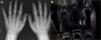

Niño de 9 años que se presenta con cuadro de 9 meses de evolución de tumefacción progresiva y bilateral de interfalángicas proximales 1, 2, 3 y 4, con patrón simétrico (fig. 1). El niño no refiere dolor, ni limitación, ni otros síntomas asociados. En la RM de las manos (fig. 2), se aprecia un aumento de partes blandas sin derrame articular ni sinovitis asociada. Se realiza una biopsia cutánea (fig. 3) que muestra una hiperqueratosis con ortoqueratosis y depósitos pan-dérmicos de colágeno. La paquidermodactilia es una fibromatosis digital progresiva benigna, descrita por primera vez en 19751, y que se caracteriza por una tumefacción progresiva de interfalángicas proximales de ambas manos en varones jóvenes; generalmente progresa a lo largo de varios años, y se estabiliza en la adolescencia, causando únicamente un defecto estético. Se proponen factores mecánicos (en pacientes con trastornos psiquiátricos o por actividades repetitivas), hormonales y genéticos como causas probables. Existe una propuesta de clasificación2 en: 1) clásica (afecta a más de un dedo y se asocia con microtraumas); 2) localizada (una sola articulación); 3) transgresiva (se extiende a metacarpofalángicas y mano); 4) familiar, y 5) asociada a esclerosis tuberosa. El tratamiento incluye control de factores mecánicos y psicológicos, infiltraciones con corticoides de depósito y cirugía; se prefieren tratamientos conservadores por el carácter benigno y la tendencia a la estabilización del proceso en la mayoría de los casos3.